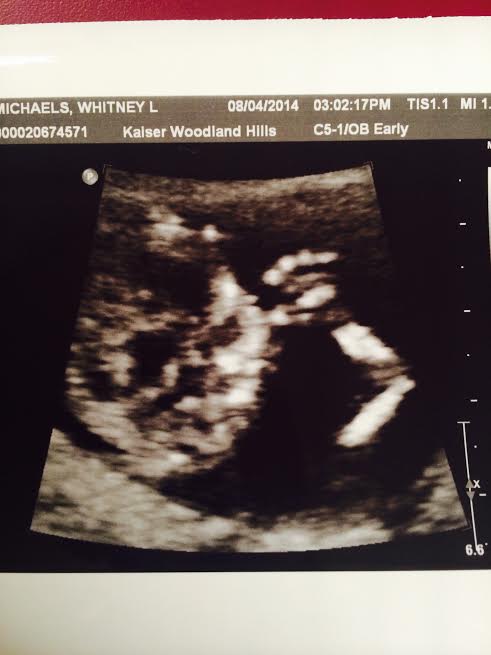

how far along: 23 weeks, 6 days {oops, a little delayed}

size of baby: a grapefruit {105-11.8 inches, 12.7-20.8 oz} not quite sure if I get this comparison…that is a VERY large grapefruit!

gender: a baby girl!